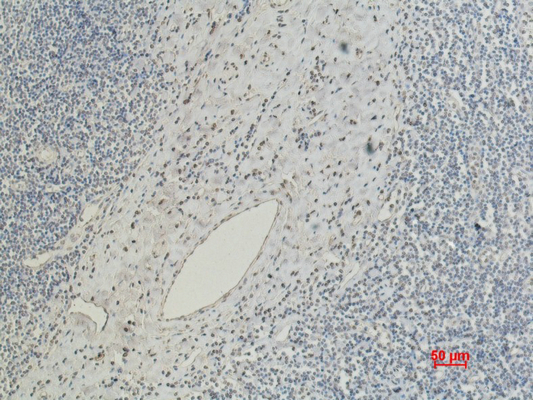

Immunohistochemistry analysis of paraffin-embedded mouse kidney tissue using CD5 antibody. High-pressure and temperature Sodium Citrate pH 6.0 was used for antigen retrieval. Negative control was used by secondary antibody only.